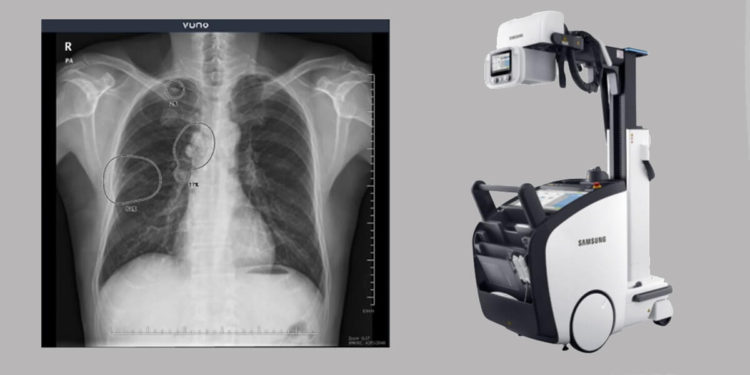

Combining VUNO Med-Chest X-ray and GM85

VUNO Med-Chest X-ray precisely and rapidly detects thoracic irregularities suggesting potentially damaging pulmonary diseases, including lung cancer, pneumonia, and tuberculosis. Notably, the AI-based chest screening solution ensures faster reading time and greater accuracy, significantly helping medical practitioners make diagnostic decisions.

Furthermore, the Samsung GM85 is a cutting-edge mobile digital radiography system delivering improved user convenience and upgraded image quality. Besides sporting a compact, lightweight design, GM85 employs a comprehensive technology range, including long-lasting batteries and ultra-fast charging.

After integrating VUNO Med-Chest X-ray with GM85, the two companies could instantly provide AI results upon screening images. The new integrated X-ray system would also become a valuable diagnostic tool with real-time analysis for ICUs and emergency rooms.